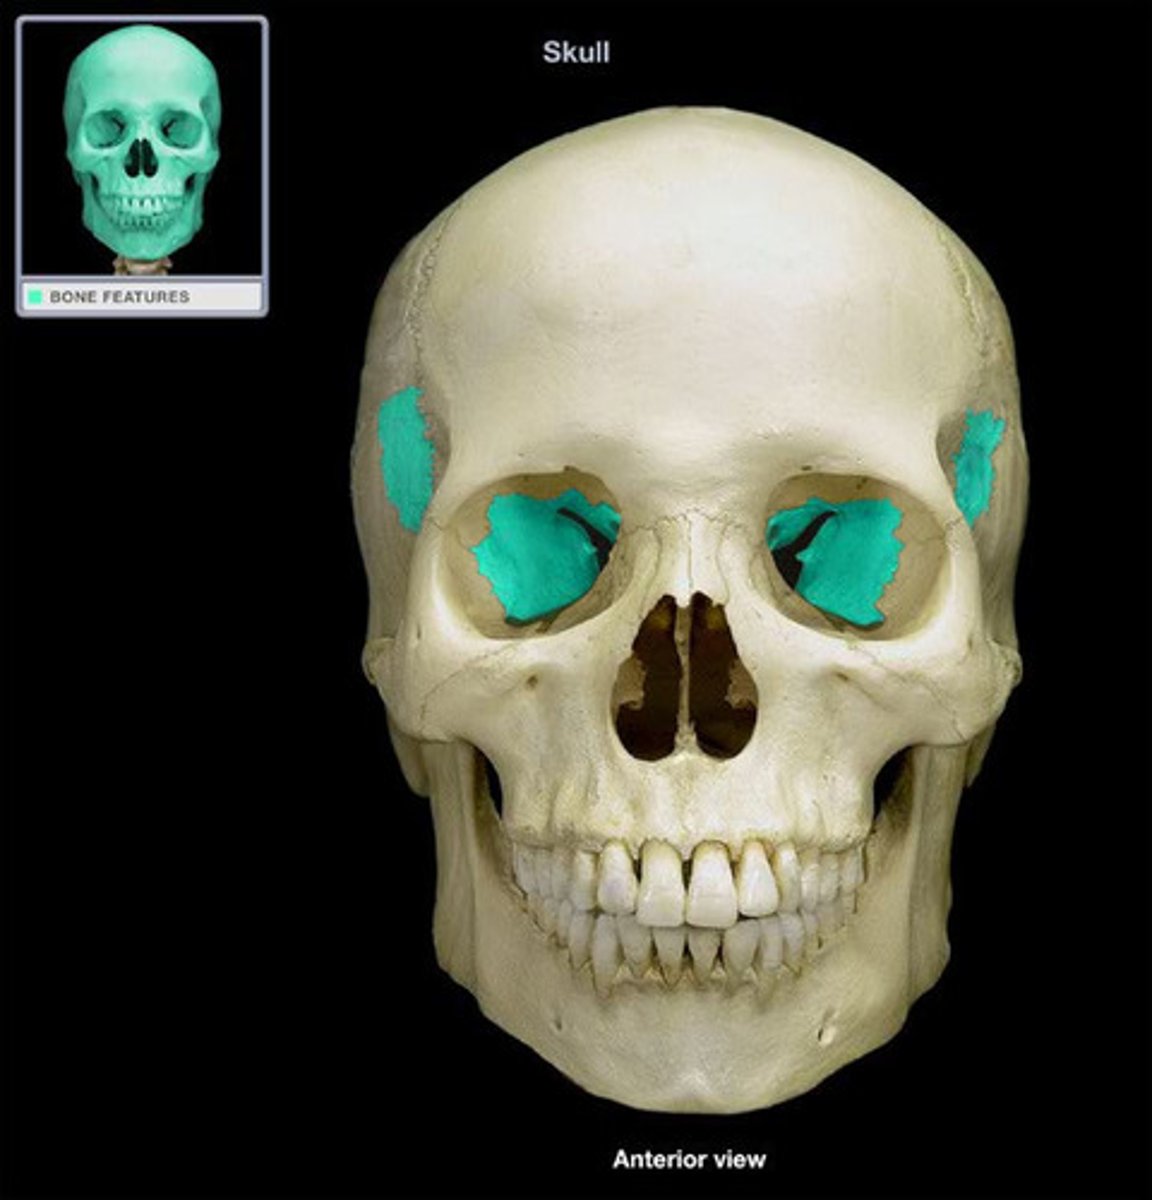

Ethmoid bone

orbital plate

cribriform plate

crista galli

perpendicular plate

labyrinths